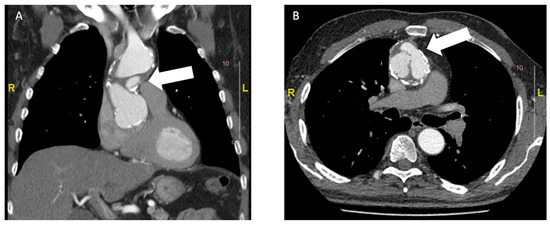

Bei einem 63-jährigen Patienten besteht ein Status nach mechanischem Aortenklappenersatz 1994 mittels St. Jude Medical© 25 mm bei kombiniertem Aortenklappenvitium, notfallmässigem Ersatz der Aorta ascendens mit 30-mm-Gefässprothese und Erhalt der Aortenklappenprothese im hypothermen Kreislaufstillstand bei Aortendissektion Typ A im Jahr 2001 und erneuter Reoperation bei Nahtaneurysmen mit Ersatz der Aorta ascendens und des Aortenbogens mit Haemoshield-Gefässprothese im Jahr 2003. Bei einer routinemässig durchgeführten Nachkontrolle durch den niedergelassenen Kardiologen wurde mittels transthorakaler Echokardiographie (TTE) ein perfundiertes Pseudoaneurysma im Bereich des proximalen Aortengrafts festgestellt (Abbildung 1). Daraufhin wurde der klinisch beschwerdefreie und hämodynamisch stabile Patient zur dringlichen Computertomographie (CT) in ein peripheres Spital überwiesen. Dort bestätigte sich der Verdacht eines Pseudoaneurysma im Sinne eines Nahthaneurysma (ca. 47 × 19 × 44 mm) ausgehend von der Aorta-ascendens-Prothese mit hochgradigem Verdacht auf Graftdehiszenz zwischen Ascendes- und Aortenbogengraft (Abbildung 2).

Abbildung 2. Die präoperative CT-Angiographie (A: frontaler Schnitt; B: transversaler Schnitt) zeigt das perfundierte Nahtaneurysma (weisser Pfeil).